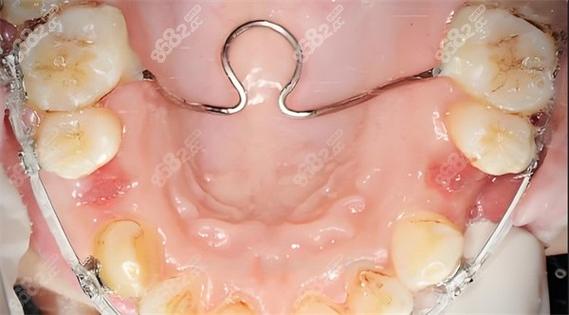

TPA的核心结构为一根“U”形或“N”形的金属丝,两端通过焊接或直接弯制形成挂钩或套管,与后牙的托槽或带环固定连接,金属丝的直径通常为0.9mm至1.2mm,根据治疗需求选择不同粗细——较粗的丝(如1.2mm)提供更强的支抗稳定性,较细的丝(如0.9mm)则更利于力的柔和传递。

其工作原理基于“生物力学作用”:通过金属丝的形变产生持续力,作用于上颌后牙及周围组织,当TPA的腭部弧度大于个体腭穹窿高度时,会对两侧后牙产生横向压迫力,防止后牙外扩;若弧度小于腭穹窿高度,则可能通过轻微的“打开”动作辅助后牙压低或前牙伸长;TPA跨越腭中缝,可限制上颌后牙的近远中移动,起到“支抗增强”的作用,确保其他牙齿(如前牙)在移动过程中后牙位置稳定。